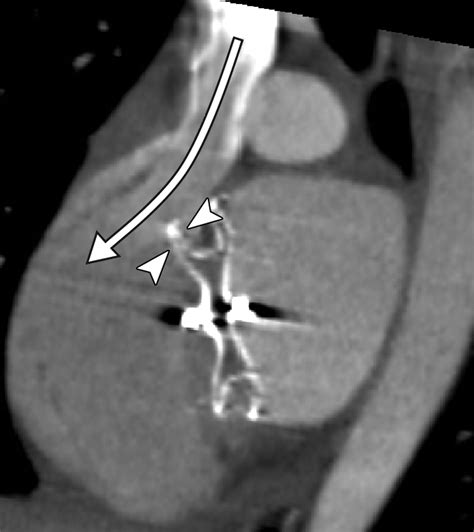

The Amplatzer Septal Occluder is specifically designed to address this by sealing the defect. It is essentially a self-expanding, double-disk device made from a flexible nitinol wire mesh. Once placed, it creates a "sandwich" effect that covers both sides of the hole, allowing the patient's own tissue to grow over the device over time, effectively healing the septal wall.

The implantation of the device is performed in a cardiac catheterization laboratory. Unlike traditional surgery, which requires opening the chest and placing the patient on a heart-lung bypass machine, this procedure is conducted through a small incision in the groin. A catheter is guided through the femoral vein up into the heart under the guidance of echocardiography or fluoroscopy.

• Deployment: The Amplatzer Septal Occluder is pushed through the catheter. The left atrial disk is deployed first to anchor the device, followed by the right atrial disk.